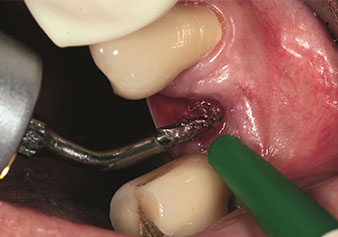

One application, which is often underestimated is the atraumatic extraction of tooth roots or root fragments in the scope of alveolar management. The fine periotomes, which are currently available in two versions (EX1 and EX2 from W&H), can also be used to remove teeth which have previously undergone special endodontic treatment or ankylosed roots with ease. This results in extraction alveoli where both the hard and soft tissue are fully intact as it is generally possible to avoid reflection.

This establishes the optimal basis for subsequent or immediate implant treatment (Figures 1 and 2 included with the kind permission of Dr Torsten Conrad, Bingen a. Rhein).

Photo: © Dr Torsten Conrad (Bingen am Rhein)